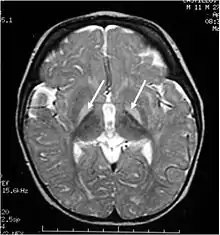

Extremely high levels of unconjugated bilirubin in plasma enables bilirubin to cross the blood-brain-barrier to reach the brain and central nervous system to impart damage. This is termed kernicterus, or bilirubin encephalopathy. Kernicterus is rare in adults but is prevalent in newborns with underdeveloped blood-brain barriers and lower albumin binding capacities, which otherwise buffers excess bilirubin in adults. To date, only 4 such cases have been published, with 3 of them associated with CN-2, the milder form of the syndrome.[28][29] The risk of developing kernicterus in CN-2 patients increases during physiological stress, such as prolonged fasting or anaesthesia.[30] In infants, a bilirubin-albumin molar ratio of >0.8 reflecting insufficient bilirubin binding is considered at risk of developing kernicterus but the indicative value in adults remains unclear.[31]

Unbound plasma bilirubin past a threshold exerts neurotoxic effects through triggering diversified metabolic cascades. It decreases oxygen consumption and increases neuronal apoptosis directly or indirectly through release of pro-inflammatory enzymes by glial cells.[32] Primary targets affected are the basal ganglia, brainstem and cerebellum due to differential tissue binding, bilirubin uptake and cell's higher sensitivity to injury.[32][33]

As this damage is irreversible, prophylactic treatment is essential to avoid critically high bilirubin levels.